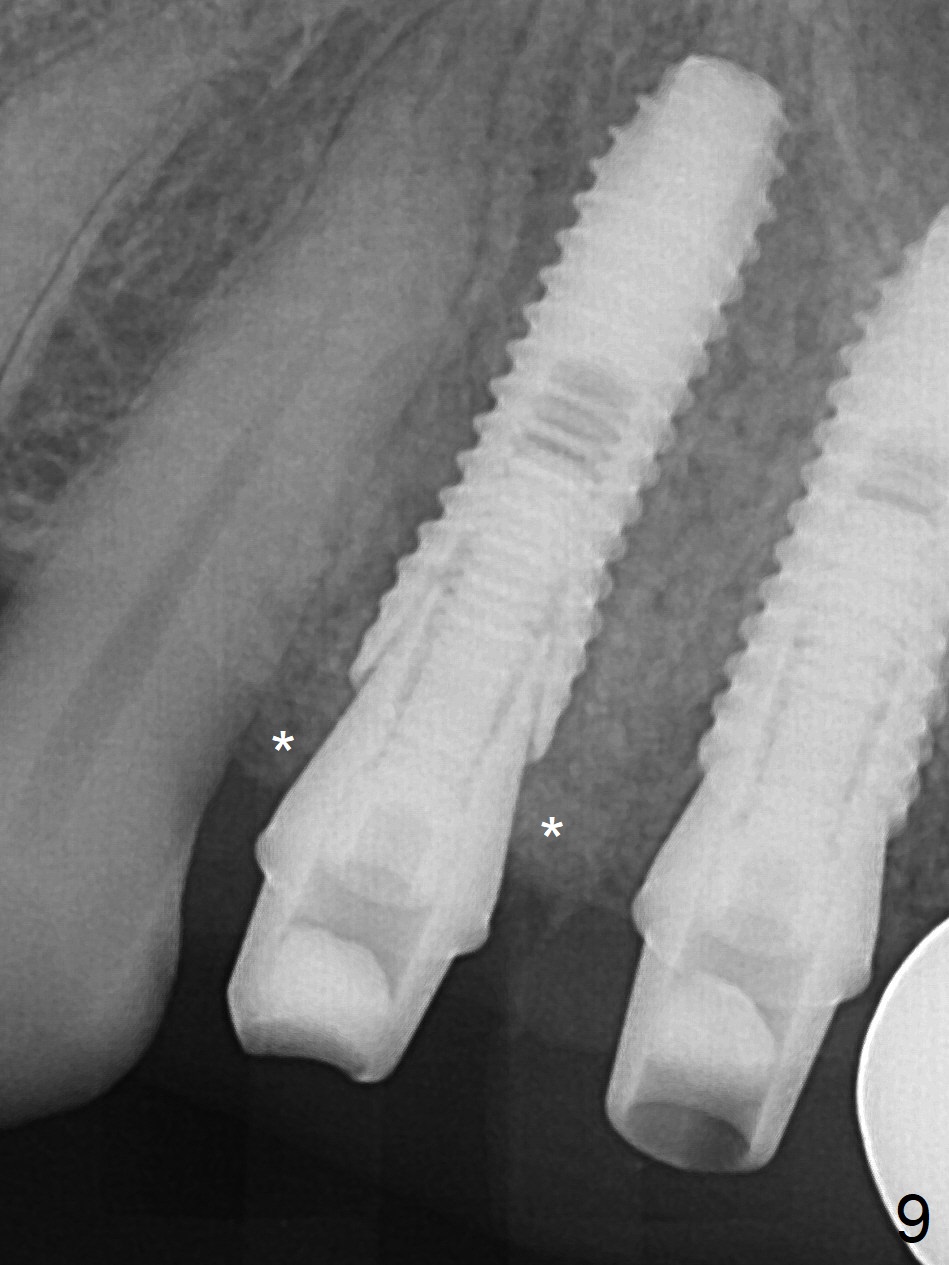

Preop photo shows palatally subgingival fracture (Fig.6). Initial depth is 15 mm at #12 after extraction (Fig.7) and then is extended to 17 mm. In fact the osteotomy is created in the palatal socket, since the septum is thin, while the buccal socket has its apical perforation. A 3.8x13 mm implant is placed (Fig.8); a 4.5x4(3) abutment and allograft are placed (Fig.9 *) prior to immediate provisional fabrication.